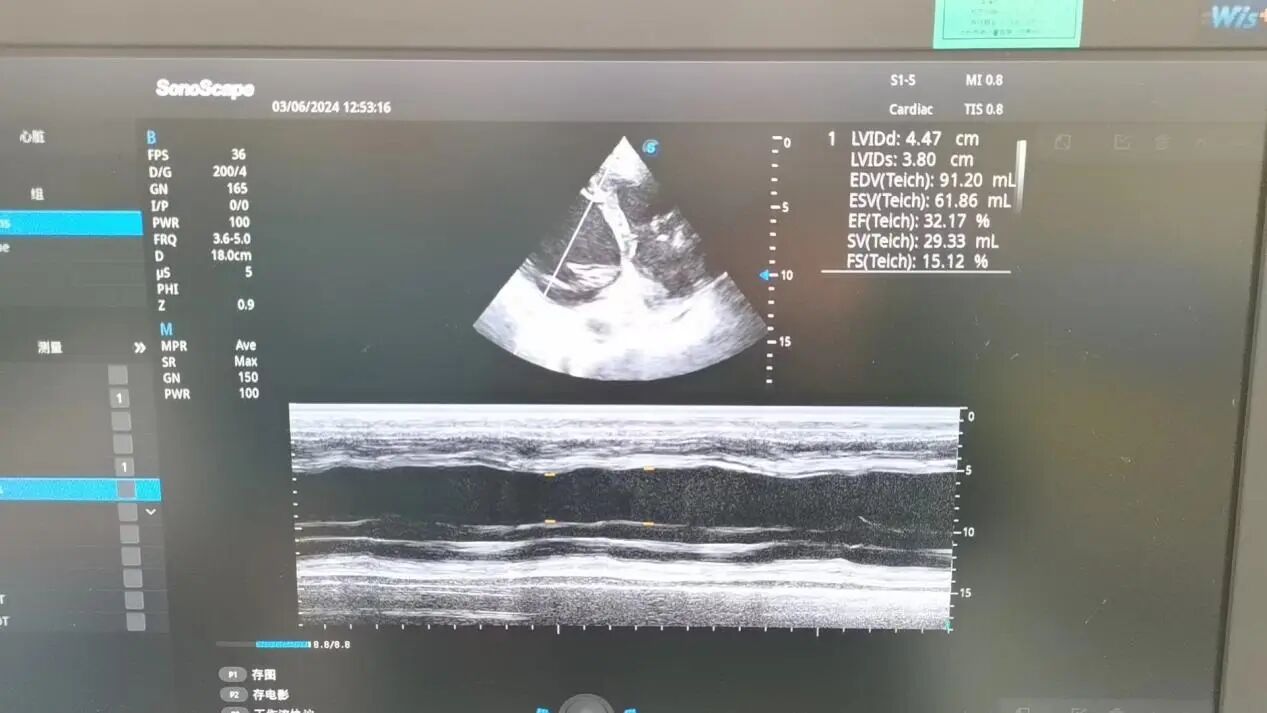

3、心脏超声:左室舒张期末内径LVEDD 73mm (正常<55mm),左室收缩期末内径LVSD 63mm (正常<35mm),EF(射血分数)35%,左室壁收缩活动节段性减低,左室收缩及舒张功能减低。

在曾庆繁院长、博士生导师兼学科带头人指导下,徐金富主治医师、雷璇住院医师行体表心脏超声。

麻醉前心脏超声